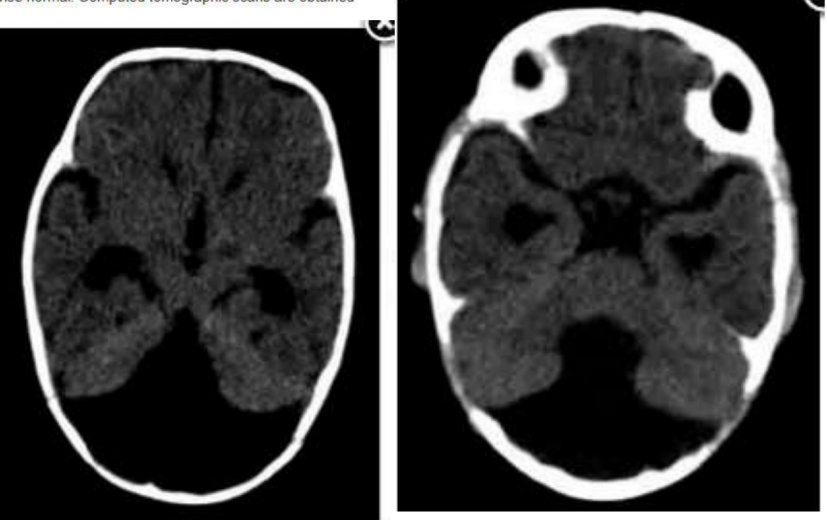

A 6-month-old infant presents with enlarging head circumference, full anterior fontanelle, splitting of the cranial sutures and developmental delay. The results of a neurological examination are otherwise normal. Computed tomographic scans are obtained

(Figures 1 and 2). What is the most likely diagnosis?

a. Dandy-Walker malformation

b. Chiari Il malformation

c. Retrocerebellar arachnoid cyst

d. Aqueductal stenosis

Dandy-Walker malformation